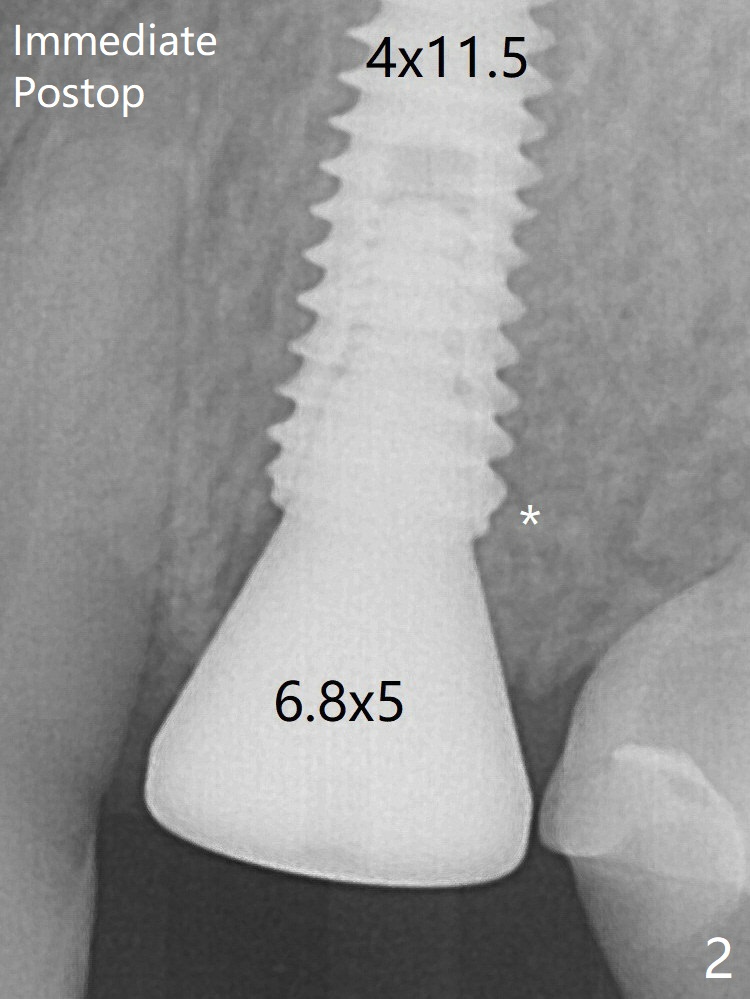

There is crestal remodeling without implant thread exposure 11 months postop (Fig.13).